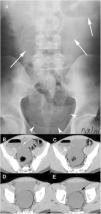

The presence of an MD in a MDCT should be suspected when a blind tubular structure connected to the terminal ileum by a neck of variable size is observed. Multiplanar 2D reconstructions images and CT enterography can help in the diagnosis. In patients with symptoms of obstruction or intestinal inflammation, the possibility of a complication secondary to a MD should be considered, especially when the terminal ileum and the vermiform appendix are normal. MDCT angiography, in cases of acute gastrointestinal bleeding, can identify contrast extravasation and accumulation of blood in the MD, and could demonstrate the persistent omphalomesenteric artery, which is diagnostic of MD. Other MDCT findings such as the presence of enteroliths or associated inflammatory changes around the MD can facilitate the preoperative diagnosis of MD complications.